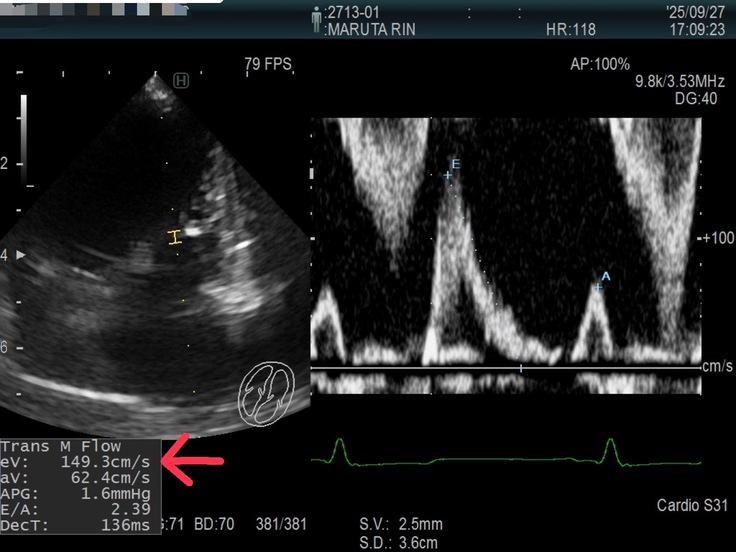

エコーの結果左心房圧が上昇しており肺水腫のリスクが高まっているみたいです。E波と言われるものが先週の126㎝から149.3㎝に上昇していました。(画像の矢印の数値)

その為に利尿剤の量が追加で増えてしまいました。